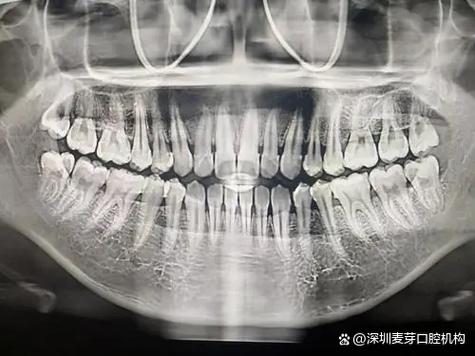

(图片来源网络,侵删)

曲面体层片(全景片)

- 原理: X射线球管和胶片/探测器围绕患者头部做同步旋转运动,获得全口牙齿、颌骨、上颌窦、下颌管等的影像。

- 优点:

- 全口视野: 一次拍摄即可显示全口牙齿及其周围牙槽骨的大致情况。

- 操作简便: 患者配合要求相对较低。

- 成本适中: 比根尖片贵,但比CBCT便宜。

- 缺点:

- 分辨率低: 图像细节不如根尖片清晰,骨吸收的细微变化难以发现。

- 几何变形和放大严重: 图像存在明显的几何变形和放大,尤其是在前牙区和下颌后牙区,对骨吸收的精确测量和判断类型(水平/垂直)非常困难。

- 结构重叠: 上下颌牙、颞下颌关节、上颌窦等结构相互重叠,可能掩盖或干扰对牙槽骨的观察。

- 辐射剂量较高: 辐射剂量显著高于单张根尖片(相当于十几到二十多张根尖片)。

- 在牙周炎中的应用:

- 初步筛查: 快速了解全口牙槽骨的大致状况,发现明显的广泛性骨吸收区域。

- 无法精确诊断: 不推荐作为牙周炎诊断和分型的首选或主要依据,因其精度不足以准确评估骨吸收的类型和程度,主要用于排除其他颌骨疾病或了解整体情况。